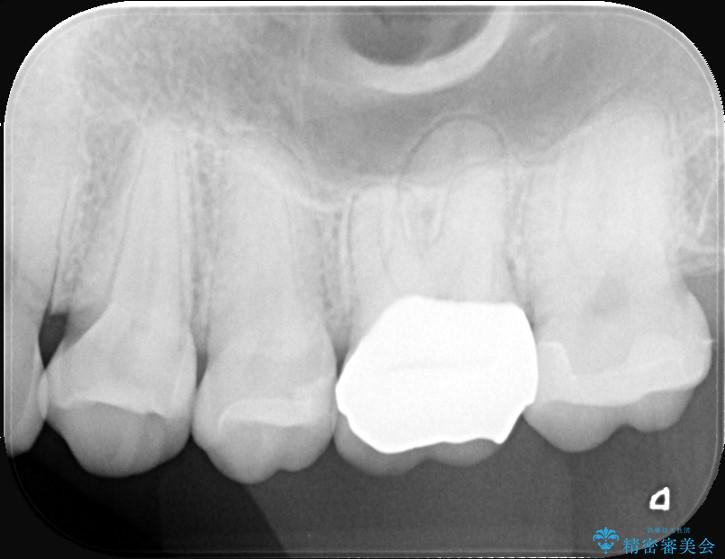

- 奥歯の虫歯治療を主訴にご来院されました。患者様から「できるだけ通院回数を少なく、早く治療を終わらせたい」というご要望があったため、短期間での完了を目指し、セラミックインレー(詰め物)とセラミッククラウン(被せ物)を併用する治療計画を立案しました。治療は精密機器を活用し、2回の来院で最終的なセラミック修復物を装着することを目指します。

今回の治療では、虫歯の大きさや深さに応じて、異なるセラミック修復法を適用しました。

比較的軽度な虫歯には、セラミックインレー(詰め物)で対応し、健全な歯質を最大限に残しました。

進行した虫歯や歯の強度が低下している歯には、セラミッククラウン(被せ物)を選択し、歯全体を保護することで破折を防ぎました。